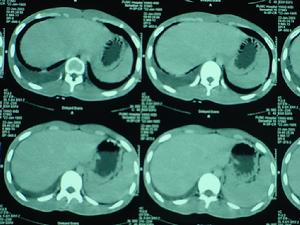

類肺炎性胸腔積液其他輔助檢查:肺的物理檢查結合胸部的X線徵象對中等量以上的積液確定較易,而少量胸腔積液則要通過細緻的檢查才能確定。前後位或側位胸片肋膈角模糊或變鈍,或膈肌模糊者提示有胸腔積液,可改變體位透視或側臥位胸片確定,此時液體散開,肋膈角或膈肌變清晰。CT對胸腔積液診斷效率更高,還可鑑別肺和胸膜病變,了解肺實質病變的位置和特徵,有助於鑑別診斷和指導治療。此外,超音波檢查也可確定有無胸腔積液存在和穿刺定位。